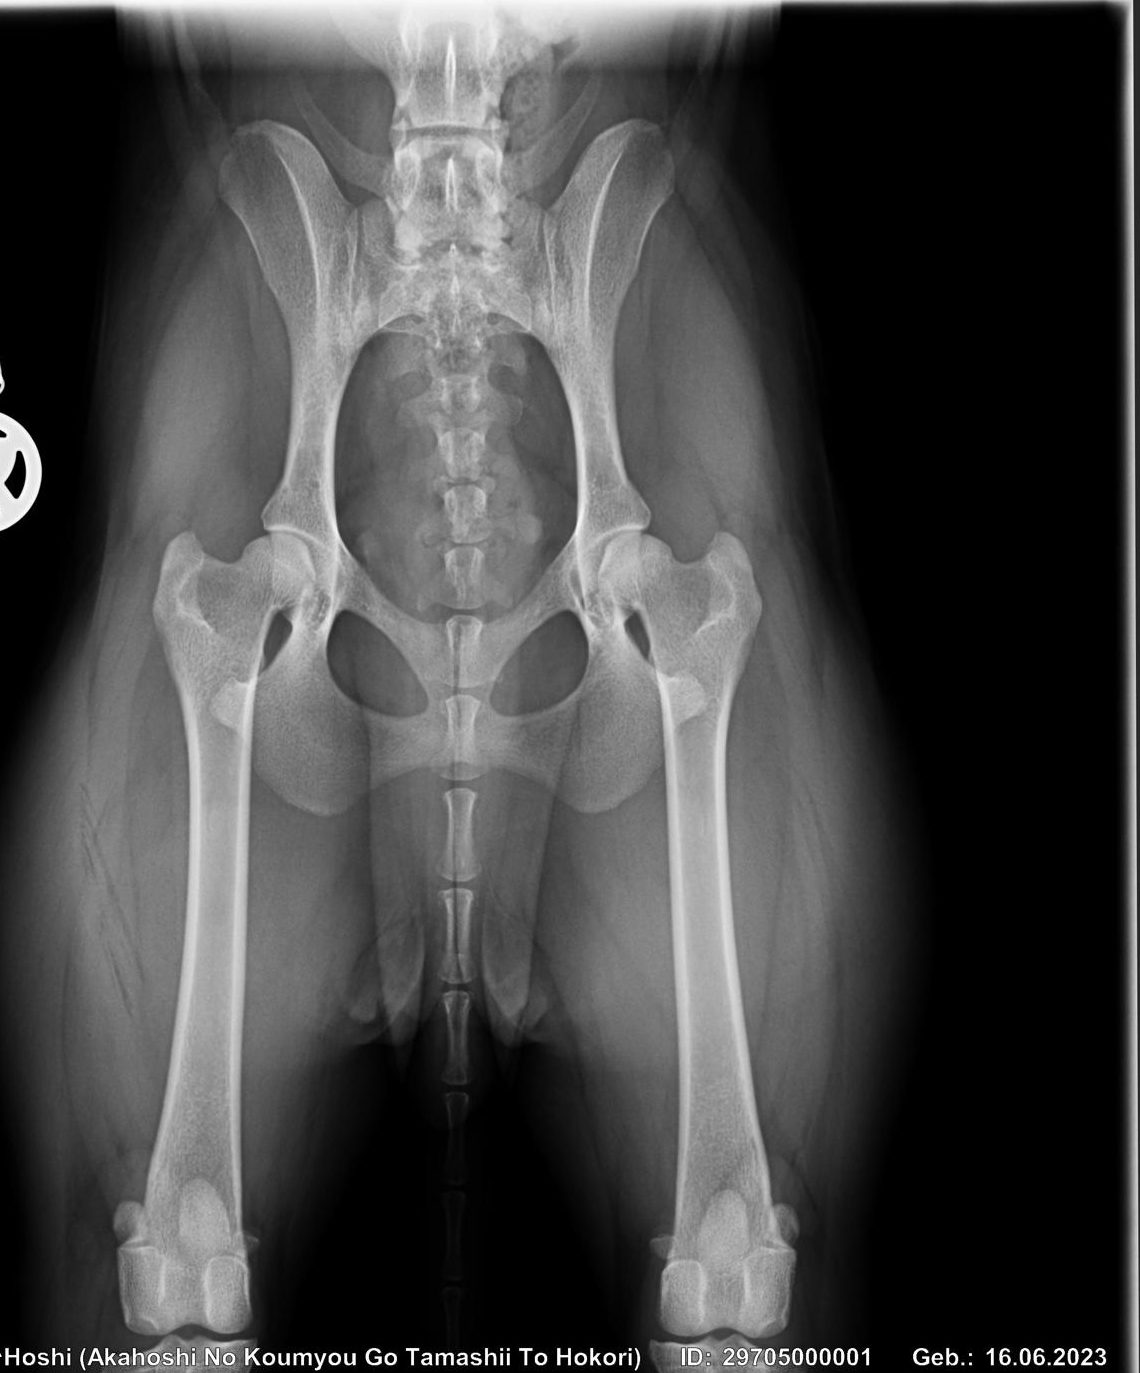

Akahoshi no Koumyo & Beniryuuhime no Suki sind beide Patella 0/0 (frei) ausgewertet worden!

Die HD Bilder liegen beim Gutachter und wir warten nun auf die offizielle Beurteilung!